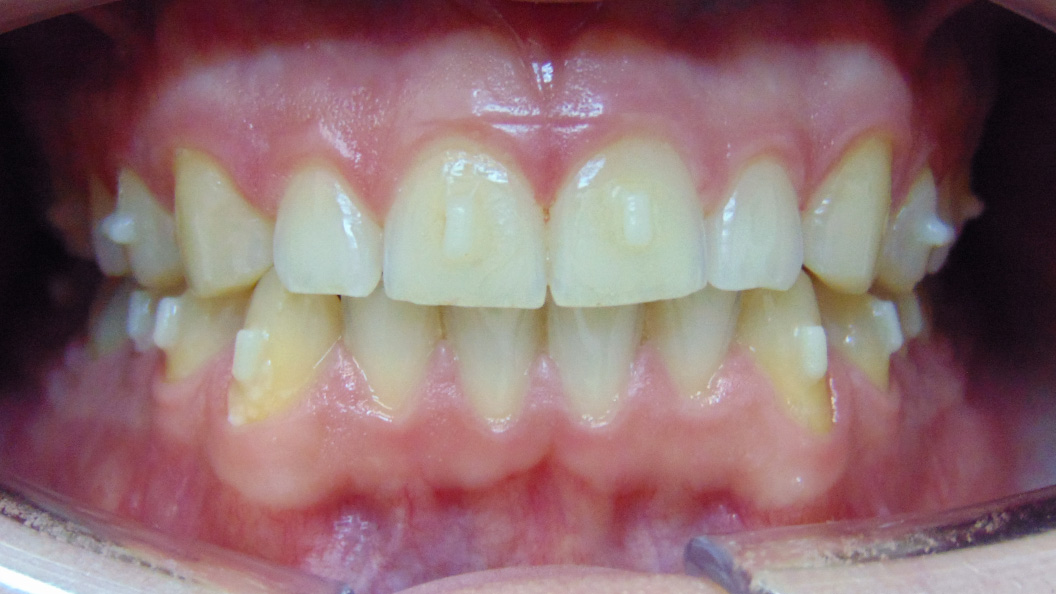

До и после лечения

В «Стоматологию Комфорта» обратился пациент с целью исправления нескольких дефектов прикуса. Проведя осмотр, врач-ортодонт Резниченко Анна Васильевна сделала заключение о наличии диастемы, тремы на верхней челюсти во фронтальном отделе. Также было диагностировано скученное положение зубов на нижней челюсти во фронтальном отделе. Врач принял решение об ортодонтическом лечении элайнерами 3D-smile.